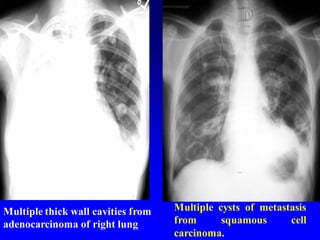

Multiple cysts of metastasis

from squamous cell

carcinoma.

Multiple thick wall cavities from

adenocarcinoma of right lung